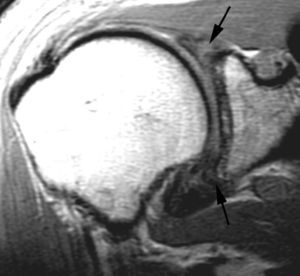

Lesiones por pinzamiento posterosuperior (posterosuperior impingement syndrome) < del LG superior con extensión posterior (SLAP tipo II-b), roturas parciales o completas del tendón del supraespinoso y pequeñas fracturas por compresión del margen posterosuperior del trocánter. Estas lesiones se producen típicamente en el atleta lanzador.

La etiología y el mecanismo de producción de estas lesiones han sido ampliamente debatidos. Jobe et al en 198930 consideraron que estas lesiones eran debidas a una laxitud de la cápsula anterior que producía una migración anterior de la cabeza humeral durante la abducción y rotación externa. En 1991, Walsh et al31, siguiendo la teoría de Jobe et al30, describieron el síndrome de pinzamiento interno o posterosuperior relacionado con una laxitud capsuloligamentosa anterior. En 1998, Burkhart et al describieron una alta incidencia de SLAP II-b en el atleta lanzador32. Estos mismos autores llegaron a la conclusión en el año 200333 de que las lesiones descritas anteriormente son producidas por una cascada de eventos originados por una fibrosis y engrosamiento de la cápsula posteroinferior y de la banda posterior del LGHI. Según estos autores, el atleta lanzador, después de múltiples movimientos de abducción y rotación externa, consigue un desplazamiento del punto de rotación y del arco de traslación del trocánter desde el centro de la cavidad glenoidea hacia arriba y hacia atrás «la zona» tal como se describe anteriormente (microinestabilidad). Todo ello conduce a un engrosamiento de la cápsula posterior que evoluciona a una restricción de la rotación interna (fig. 34). A esta restricción se la considera el punto de origen de la cadena de lesiones que conducen a lo que se llama el «brazo muerto» (the dead arm) que representa el final de una carrera profesional deportiva. La restricción de la rotación interna se la conoce bajo las siglas de GIRD (glenohumeral internal rotation deficit). Sin embargo, no queda claro si la traslación posterosuperior del centro de rotación en el atleta sucede antes o después de la formación de cicatriz y engrosamiento capsular posterior.

Cuando el deportista consigue crear, a través del entrenamiento, este desplazamiento posterosuperior del centro de traslación o bien tiene lugar a través del engrosamiento de la cápsula posteroinferior, el hombro llega a conseguir una rotación externa de más de 150 grados en abducción a 90 grados. En este momento se llega a un punto crítico, en el cual la tensión que se produce a nivel de la inserción del TLB, en el borde superior del LG, conduce a un «arrancamiento» del mismo, con extensión de la lesión hacia la parte posterior (SLAP II-b); a este mecanismo se le conoce como peel back (fig. 35).

Una vez que se ha producido la lesión SLAP II-b, la continuación de las fuerzas de extrema rotación externa conducen a una torsión repetitiva del tendón supraespinoso, que lleva a una rotura parcial o completa del mismo (fig. 36).

Fig. 36.--GIRD (glenohumeral internal rotation deficit). Resonancia magnética (RM) coronal oblicua T2 con supresión de grasa donde se aprecia una lesión de SLAP (superior labrum anterior posterior) (flecha larga), una rotura parcial del supraespinoso (cabeza de flecha) y un engrosamiento capsular inferior (flechas cortas).